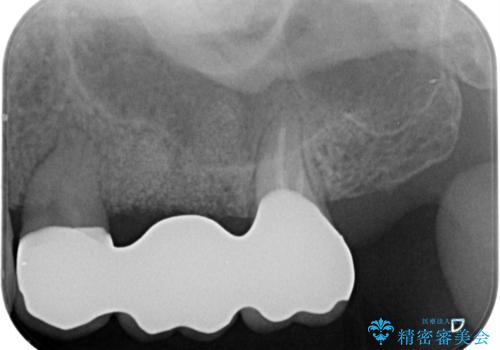

ラミネートベニヤの破折 ジルコニアクラウンによるやり替え

- 欠けてしまった前歯のラミネートベニヤと見た目の改善を求めて来院されました。

歯の大きさの不揃いと、虫歯の再発を認めたためラミネートのやりかえではなく一挙に問題の解決のできるジルコニアクラウンでの治療を計画します。